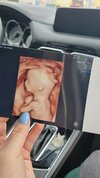

mój nie był jakiś bardzo spłaszczony ale tez była taka kropelka, zdjęcie pierwsze te płaskie z 26dpt, a drugie z 33dpt(dopiero tu było serce)

• IMG_1882.jpg

IMG_1882.jpg

120,9 KB · Wyświetleń: 76

• IMG_1903.jpg

IMG_1903.jpg

146,1 KB · Wyświetleń: 75